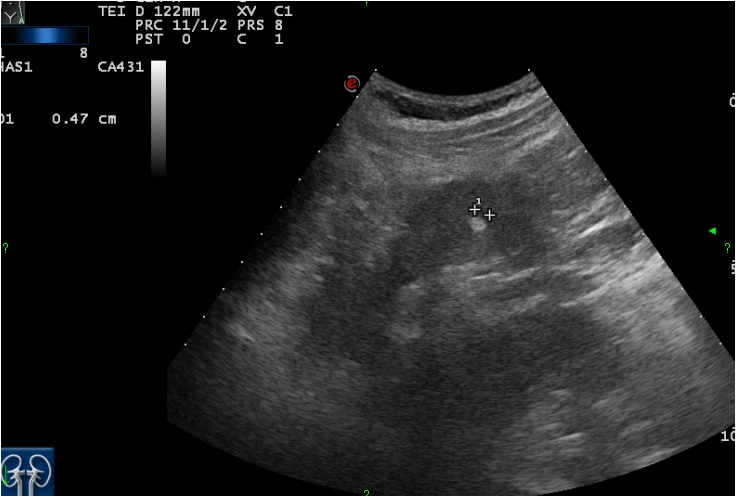

Ultrasonography (US), which is an extensively used and a widely available method, is often the first step in the diagnostic work up. During a regular abdominal US scan both kidneys are examined. Sensitivity of the US examination is significantly lower than of a CT scan, still important clinical questions can be answered with this technique. When a tumor is visualized, it is usually a hypoechoic, relatively well circumscribed mass.

Image

Figure 3. Kidney tumor on US